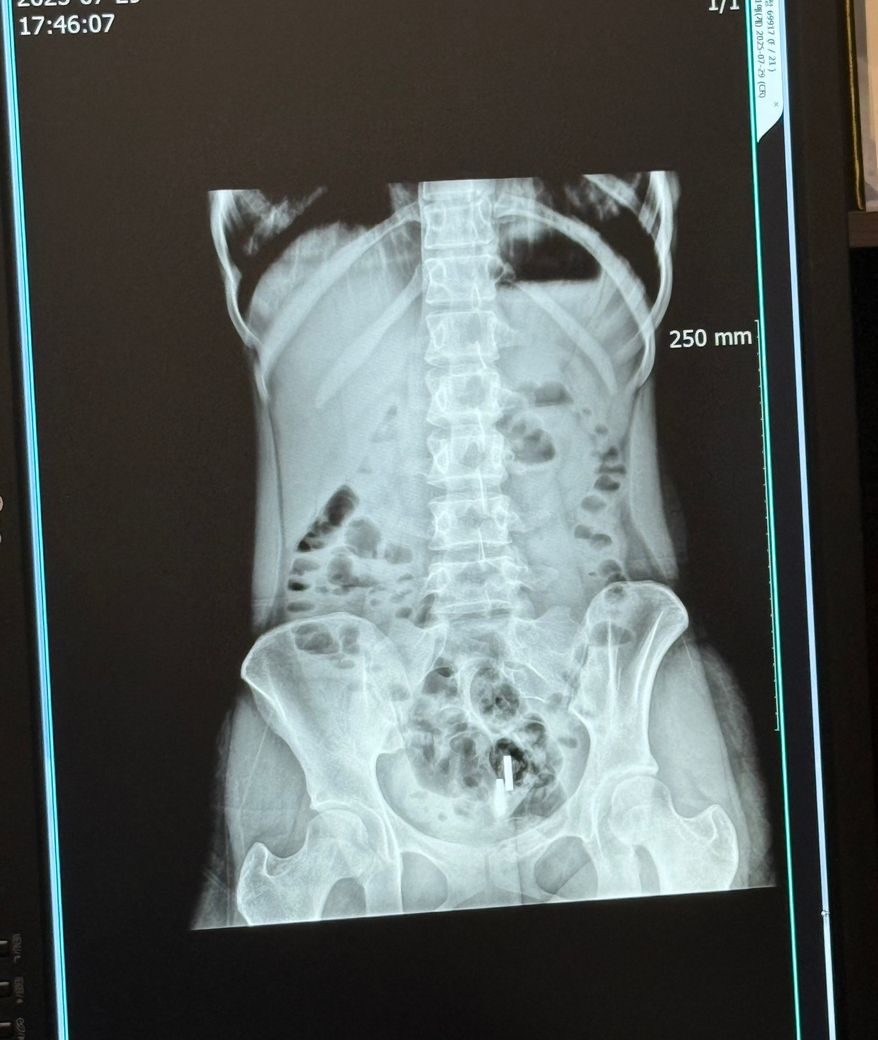

장염엑스레이 사진 봐주세요 / 여자 20대

병원다녀왔는데 설명을 못들어서요ㅠㅠ 어떤 상태인가요? 심한 급성 위장염이라하는게 사진에 대해 알고싶어서 질문 남깁니다!!

엑스레이 사진을 통해서는 급성 위장염 등에 대한 자세한 평가가 가능하지 않습니다. 각설하고 올리신 복부 엑스레이 사진에는 장 내에 비특이적인 가스 패턴을 보이며 가스가 꽤 차 있어 보입니다. 설사를 많이 할 경우에 보일 법한 소견으로 사료됩니다.